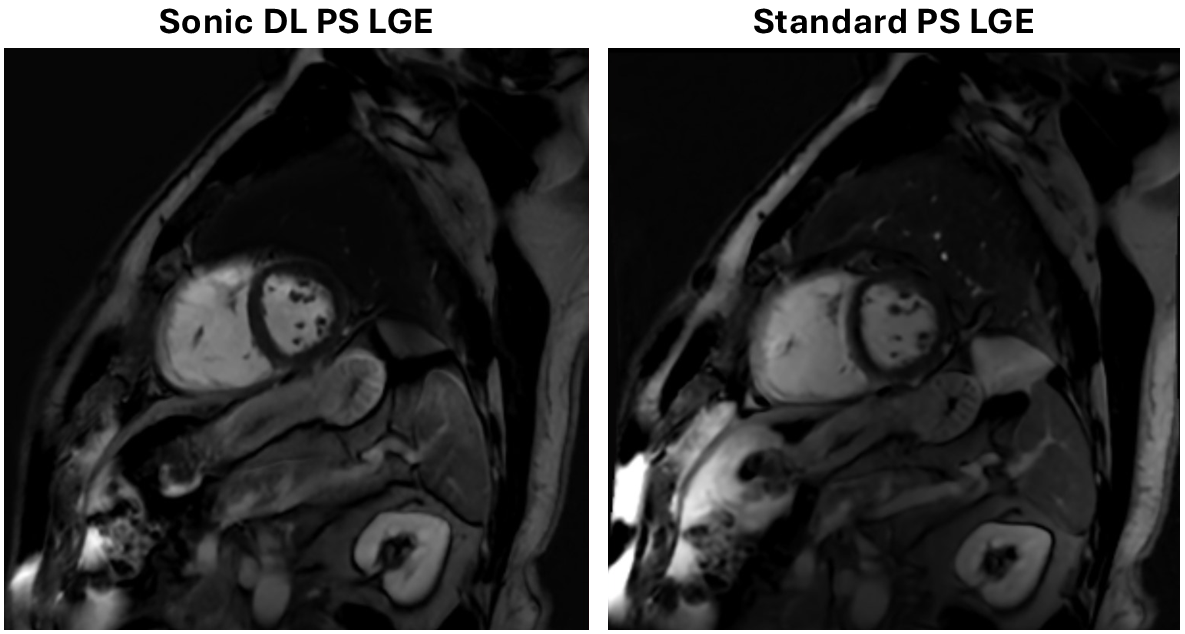

Results: There was no statistically significant difference between the two acquisitions in terms of image quality, with average Likert scores of ~4.1-4.2 from each reader for each acquisition. Artifact presence was also similar between the two acquisitions. The highly accelerated version was relatively more preferred by both readers (Reader 1: 18 vs. 12 with 27 no preference; Reader 2: 23 vs. 11 with 23 no preference). Figures 1 and 2 shows example images for patients with and without any visible abnormalities, respectively.

Figure 1: Comparison of Sonic DL and standard PS LGE acquisitions in a patient with an abnormality. The higher spatial resolution of the SONIC DL acquisition helps improve visualization. A representative slice is shown for each acquisition from the same patient.

Figure 1: Comparison of Sonic DL and standard PS LGE acquisitions in a patient with an abnormality. The higher spatial resolution of the SONIC DL acquisition helps improve visualization. A representative slice is shown for each acquisition from the same patient.